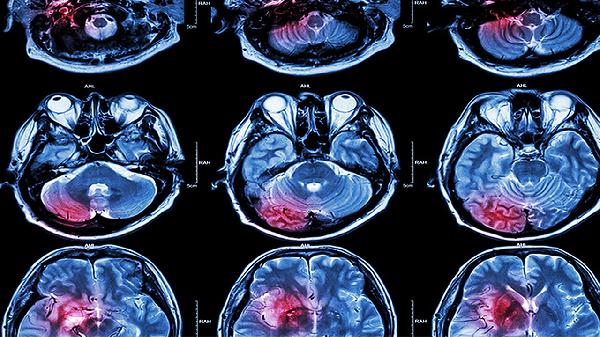

脑溢血患者使用中药治疗的效果需结合病情严重程度和阶段判断,急性期以西医抢救为主,恢复期可配合中药辅助调理。中药治疗脑溢血主要有活血化瘀、通络开窍、补益肝肾等作用,但需严格遵医嘱使用。